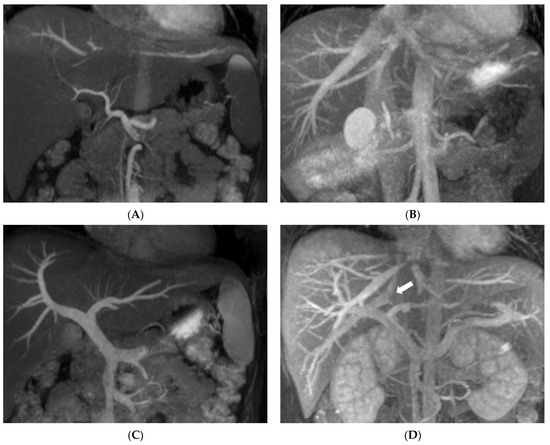

3. Results